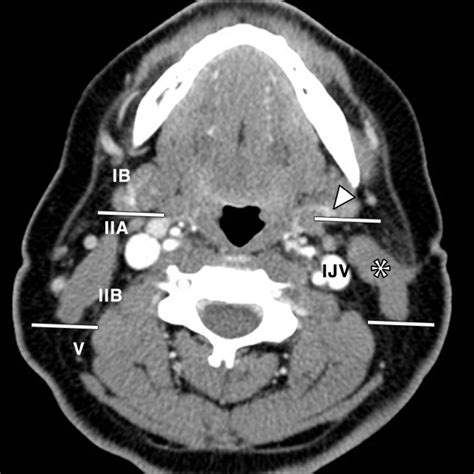

A CT scan of neck, often referred to as computed tomography, is a sophisticated diagnostic imaging procedure that utilizes X-rays combined with computer processing to create detailed, cross-sectional images of the structures within your neck. Whether your physician is investigating a persistent lump, evaluating unexplained pain, or monitoring a known condition, this imaging tool provides a level of clarity that standard X-rays cannot match. By capturing slices of the neck’s anatomy—including the thyroid gland, lymph nodes, blood vessels, and spinal structures—doctors can pinpoint abnormalities with remarkable precision, making it an essential component in modern diagnostic medicine.

Medical professionals order a CT scan of neck for a wide variety of reasons. Because the neck is a complex area housing vital pathways for breathing, swallowing, and blood flow to the brain, it is crucial to have accurate diagnostic data. This scan is frequently used to evaluate issues that require detailed visualization beyond what a physical examination can reveal.

• Tumor Staging: Assessing the size, location, and potential spread of cancers within the head and neck region.

• Vascular Evaluation: Checking for narrowing or blockages in the major blood vessels leading to the brain.